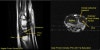

MRI에서 관찰할 수 있으나 정확도가 많이 떨어집니다.

Gold standard는 관절경(Arthroscopy)입니다.